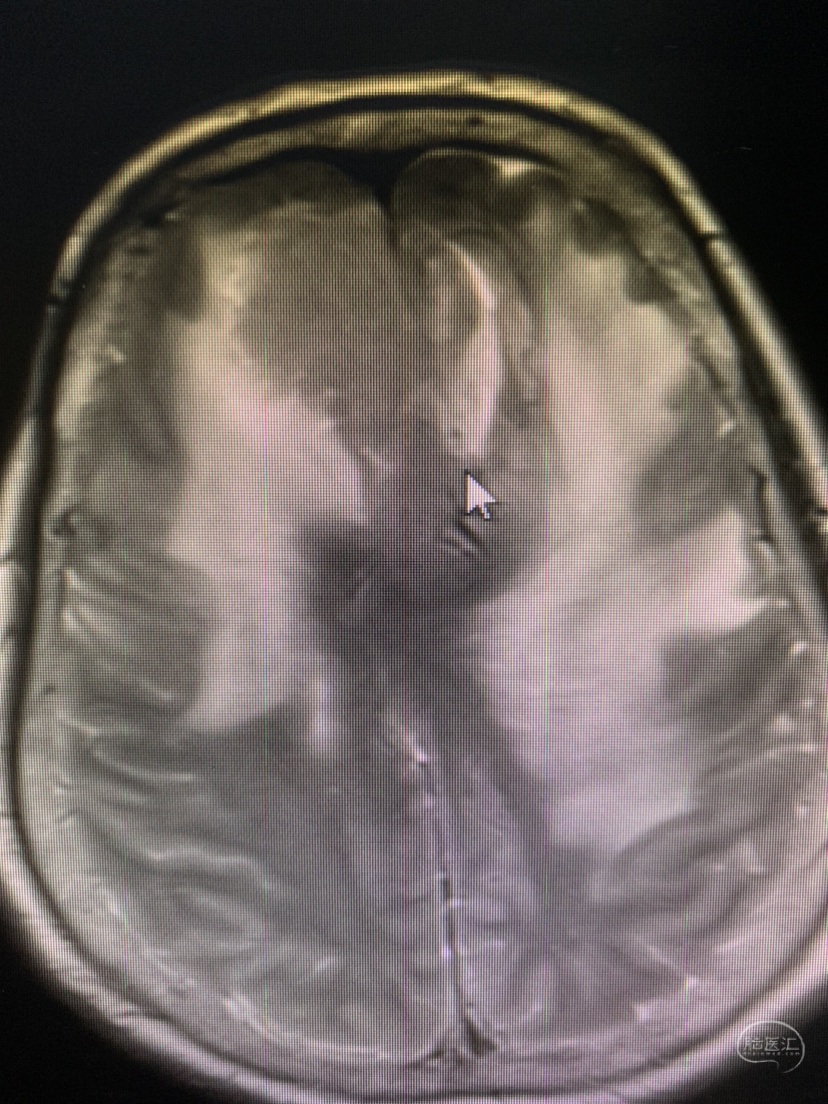

术前术后对比